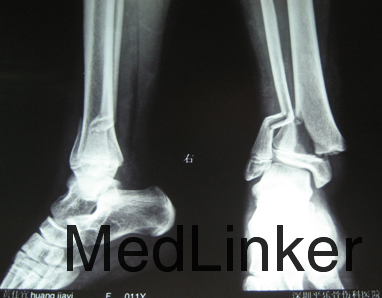

患者12岁。主诉:左踝关节疼痛活动受限8小时。现病史:8小时前摔伤,伤后出现左踝关节疼痛活动受限,急诊送至当地医院,行左踝关节正侧位DR,提示为:左胫骨远端骨折,为求进一步治疗来我院就诊,发病以来患者神志清楚,无发热,无恶心呕吐,近期体重未见明显变化。

查体:未见明显外伤口,左踝关节肿胀明显,压痛及叩击痛受限,可触及骨擦音骨擦感,左脚感觉正常,各足趾活动灵活,足背动脉搏动有力,末梢血运良。辅助检查:左踝关节正侧位DR:左胫骨远端骨折

诊断:左胫骨远端骨折 治疗:消肿止疼治疗,择期行骨折闭合复位克氏针内固定术